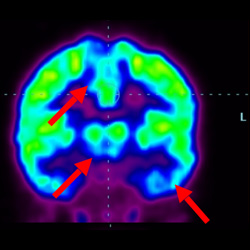

細(xì)胞治療前 PET CT 掃描顯示神經(jīng)組織中的藍(lán)/黑色區(qū)域,表明腦癱引起的大腦損傷。

腦癱細(xì)胞療法, 腦癱治療

細(xì)胞治療后,藍(lán)色和黑色區(qū)域減少,并且看到更活躍的區(qū)域。這表明損傷減少并改善了大腦功能。

這證明細(xì)胞療法是治療腦癱兒童安全有效的方法。細(xì)胞療法可以更新大腦損傷的核心,并且可以通過 PET CT 掃描來(lái)監(jiān)測(cè)大腦的改善情況。這些細(xì)胞療法與標(biāo)準(zhǔn)治療一起促進(jìn)腦癱兒童的生長(zhǎng)和改善。